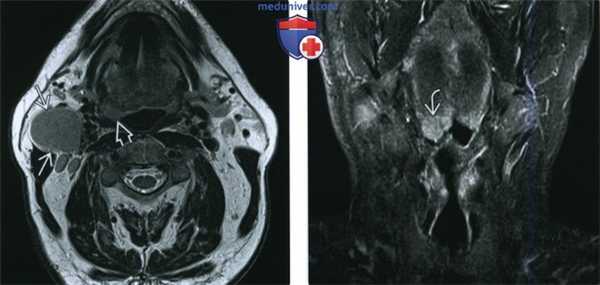

(Слева) При МРТ Т2ВИ в аксиальной проекции визуализируется патологически измененный солидный лимфоузел уровня IIА. Определяется также неявное асимметричное утолщение миндалины, которое, хотя и может быть вариантом нормы, но при отсутствии других изменений, которые могли бы объяснить лимфаденопатию, позволяет порекомендовать биопсию.

(Справа) При МРТ Т2ВИ FS в корональной проекции у этого же пациента определяется гиперинтенсивный сигнал в язычной миндалине справа. Несмотря на то, что асимметрия укладывается в границы нормы, злокачественная лимфаденопатия делает ее подозрительной находкой. В итоге подтвердился ВПЧ(+) ПКР язычной миндалины.